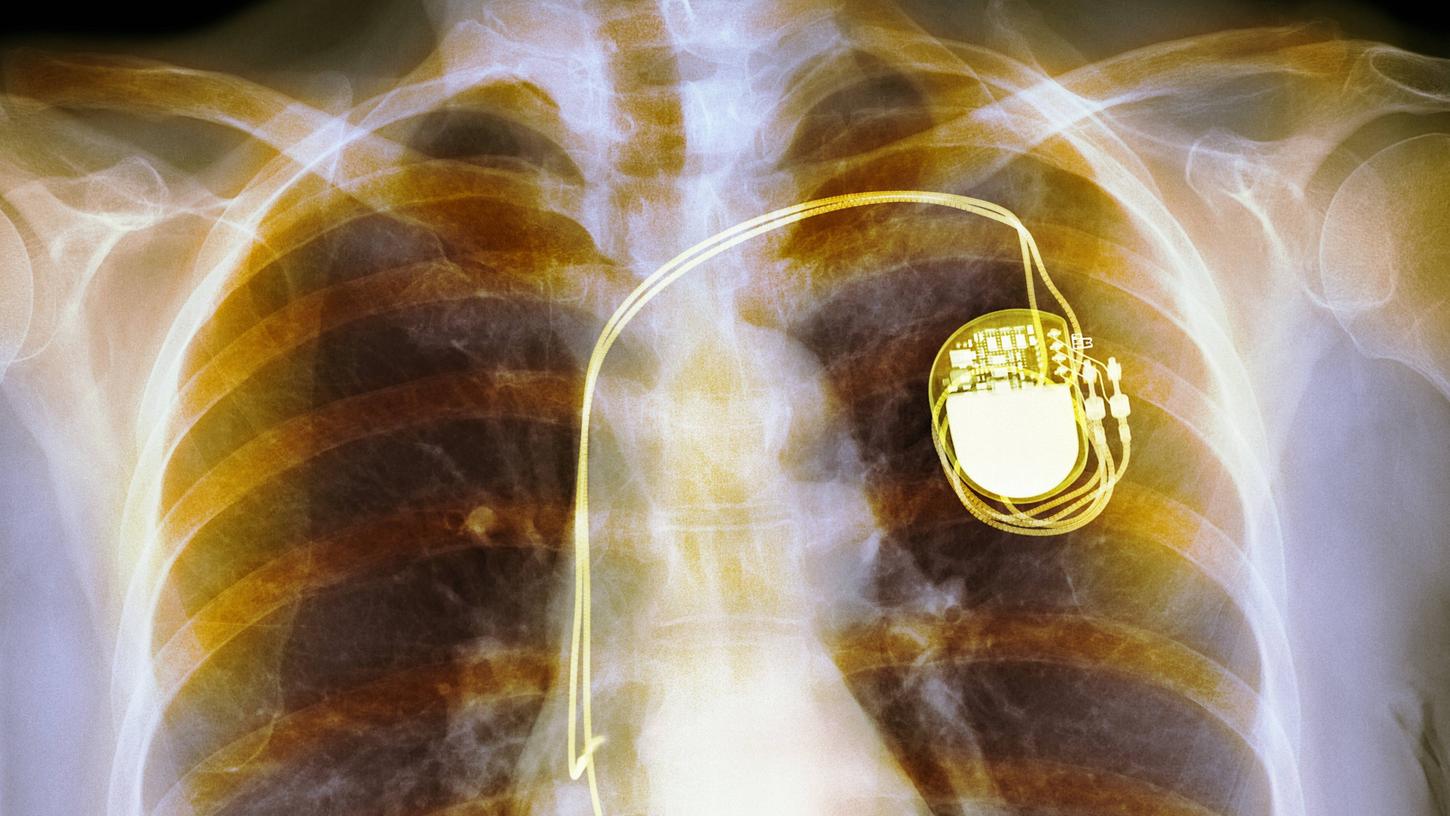

Wie funktioniert der Herzschrittmacher?

Das Gerät, etwa so groß und schwer wie zwei aufeinanderliegende Zwei-Euro-Münzen, wird über einen Hautschnitt unterhalb des Schlüsselbeins eingesetzt. Von diesem Aggregat führen Elektroden (Sonden) durch eine Vene in die Herzkammer oder Vorkammer. Diese Sonden – je nach Bedarf und Zusatzfunktionen eine, zwei oder auch drei – regen das Herz elektrisch zum Schlagen an, wenn es Störungen gibt.

Die Operation dauert im einfachsten Fall eine halbe Stunde, schildert Karsten Pohle – aber auch bis zu drei Stunden, wenn bei einem vorgeschädigten Herzen die Verankerung der Sonden Probleme bereitet. Bei den meisten Patienten genügen örtliche Betäubung und Dämmerschlaf; in der Regel bleiben sie für eine Nacht im Krankenhaus.

Neuere Herzschrittmacher sind so gut wie nicht mehr störungsanfällig gegenüber anderen Elektrogeräten; sogar Kernspintomografie-Untersuchungen (MRT) werden so für die Träger möglich. Da die Sonden der empfindlichste Geräteteil sind, entwickelt sich die kabellose Technik weiter. Bislang gibt es einen Herzschrittmacher ohne Sonden aber erst im Einkammersystem, was nur für einen Bruchteil der Patienten infrage kommt.